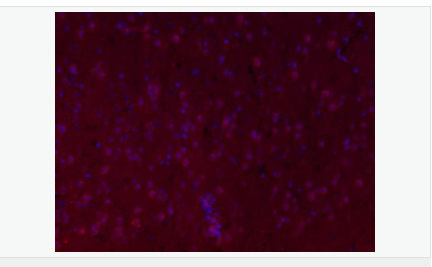

交叉反應(yīng):Mouse,Rat(predicted:Human,Pig) 推薦應(yīng)用:IHC-P,IHC-F,IF,ELISA

| 產(chǎn)品應(yīng)用 | ELISA=1:5000-10000 IHC-P=1:100-500 IHC-F=1:100-500 IF=1:100-500 (石蠟切片需做抗原修復(fù)) not yet tested in other applications. optimal dilutions/concentrations should be determined by the end user. |